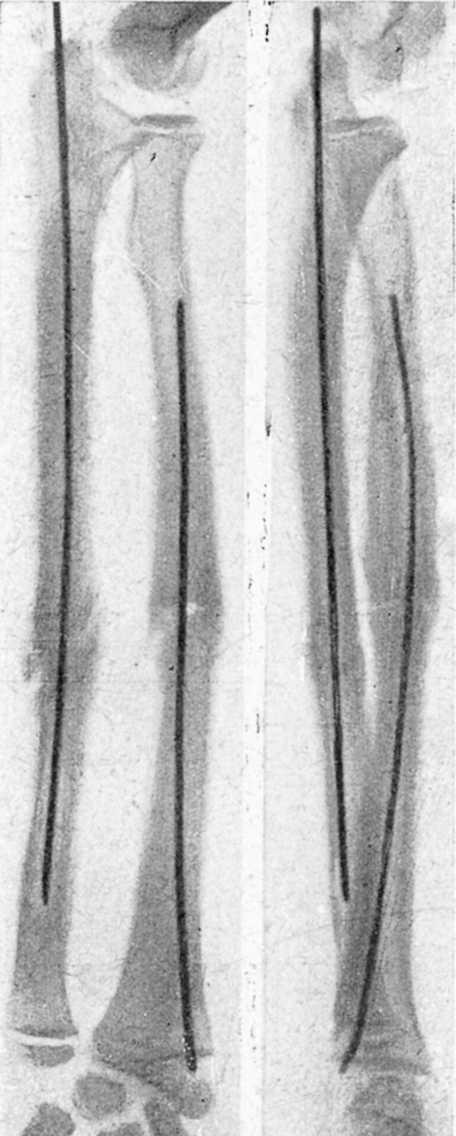

Figura 4. Enclavijamiento mixto en una pseudoartrosis de cúbito y radio, previo refrescamiento de fragmento. Fue utilizado alambre en cúbito por no disponer entonces de tallo suficientemente largo. La misma, una vez obtenida la consolidación.

Figura 5. Fractura doble, antebrazo; enclavijamiento cerrado con alambres.